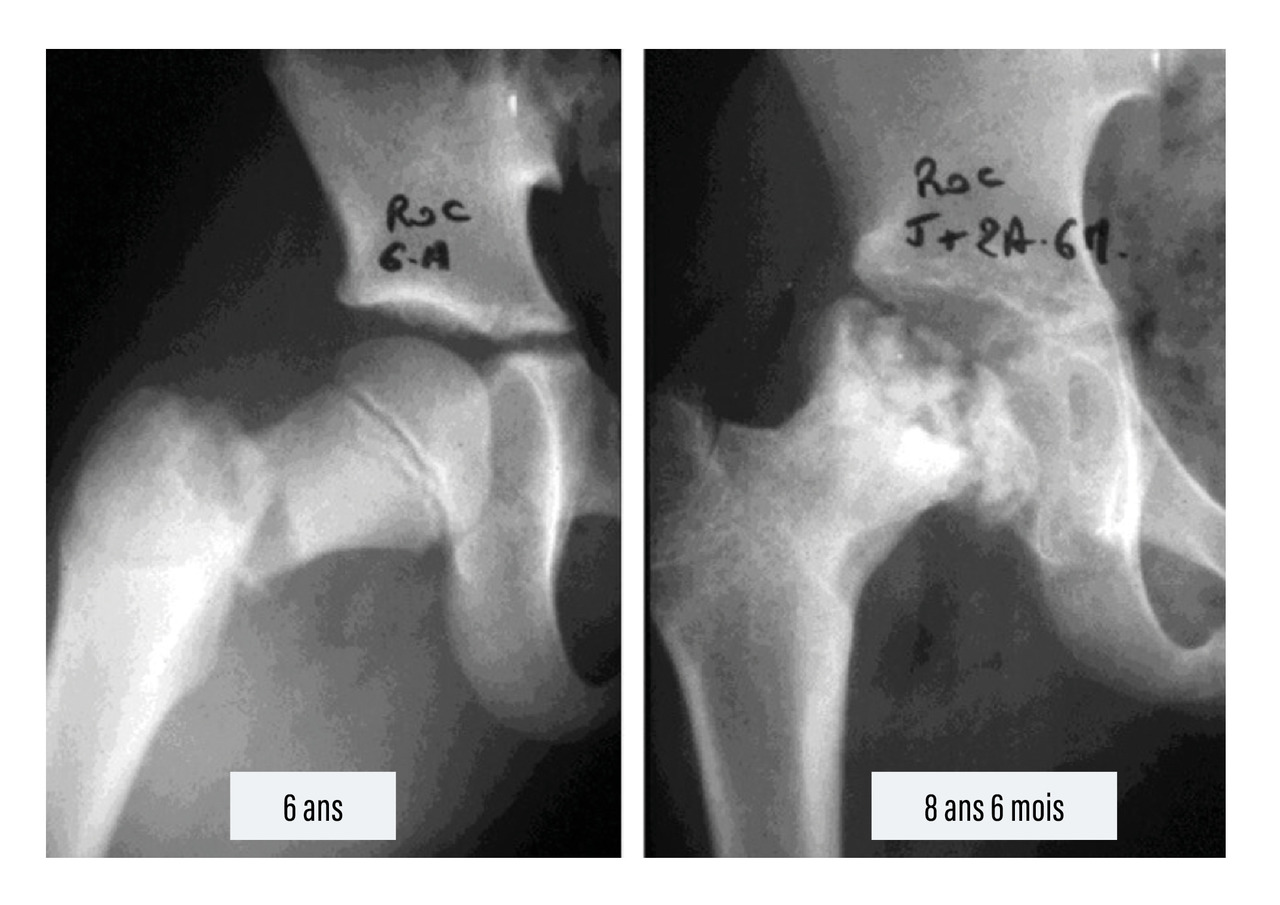

Enfin, certaines complications peuvent survenir tardivement :

• les nécroses épiphysaires par lésions ischémiques, qui concernent surtout la tête fémorale, après fracture du col15 (fig. 11), la tête radiale et le condyle externe du coude ;

• les raccourcissements et les désaxations des membres par atteinte du cartilage de croissance (épiphysiodèse) ;16

Pour les fractures touchant les zones de croissance (fractures-décollements épiphysaires), la complication la plus redoutable est le pont d’épiphysiodèse. Si le pont est central, il entraîne un arrêt de croissance du cartilage de l’os atteint. Si le pont est périphérique, il entraîne une déviation progressive de l’os atteint. Cette complication est d’autant plus importante que l’enfant est jeune et que la fracture survient sur un segment avec un fort potentiel de croissance (près du genou et loin du coude).8